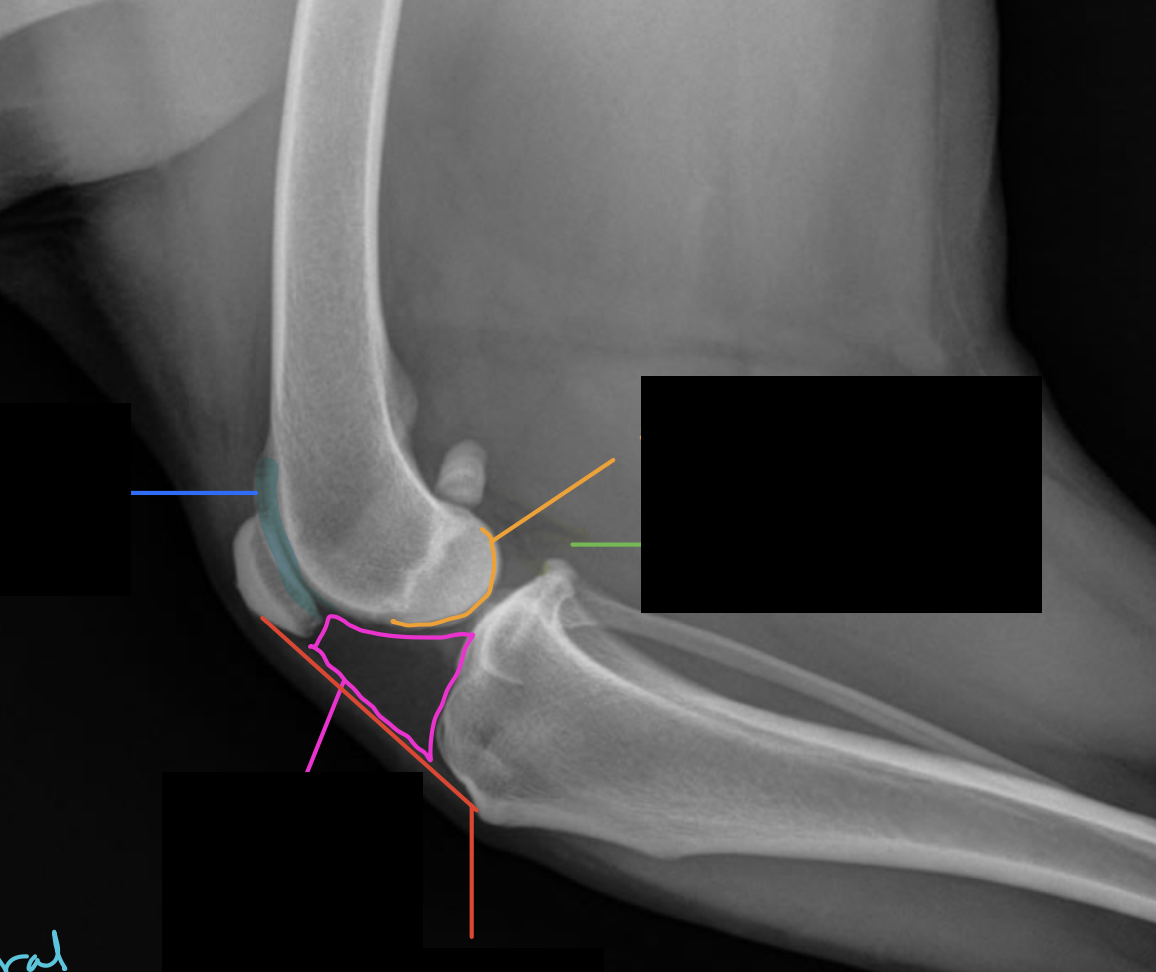

Label the following colored structures

A

blue: smooth trochlear groove

pink: infrapatellar fat pad

red: patellar ligament

green: fascial planes

orange: femoral condyles

What pathology is going on here?

purple: osseous proliferation

red: patellar ligament angle change

pink: soft tissue opacity increase - cranial aspect of joint

green: lost fascial planes